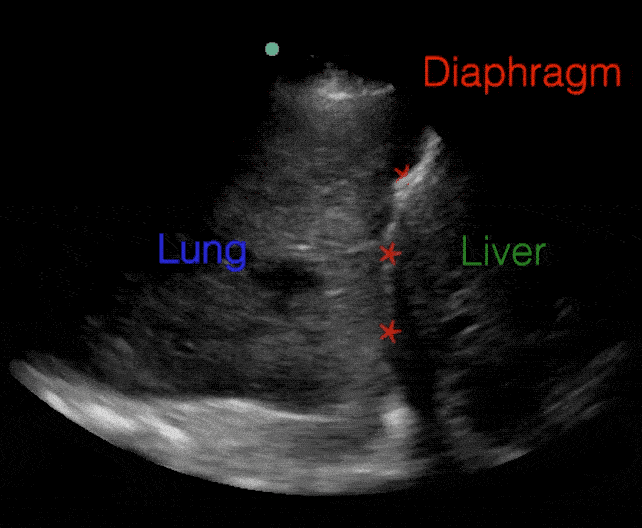

C Profile (Consolidation):

• Non-aerated, fully consolidated lung has the appearance of liver

• "Hepatization"